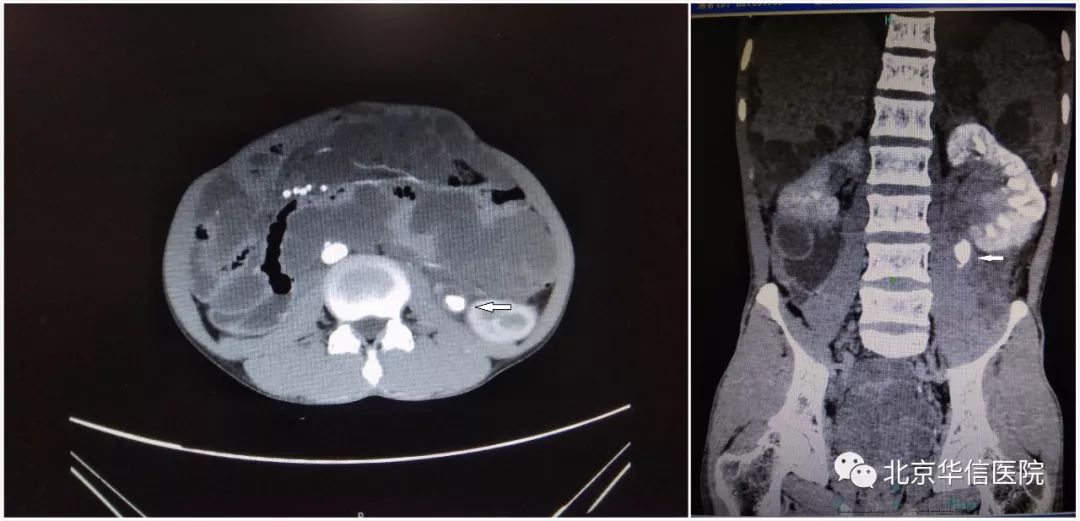

手术前腹部CT示患者腹腔内大量假粘液瘤及左输尿管结石合并左肾积水

结果显示,患者左侧尿路呈机械性梗阻,左侧肾盂及结石以上输尿管积水,血肌酐139.0 μmol/L,但左肾前有假粘液瘤包绕,后紧邻腰大肌,穿刺通道选择有限。“我们要细心、耐心、精心地做好手术,争取一次穿刺成功!”为避免对周围组织的损伤,保护患者肾功能,我们采用了微通道经皮肾镜激光碎石术。经过超声立体定位并与CT片比对确定好穿刺点,建立碎石通道、粉碎结石、放置输尿管支架……手术一气呵成,肾穿刺通道一次成功,取出全部结石,术中几乎无出血。